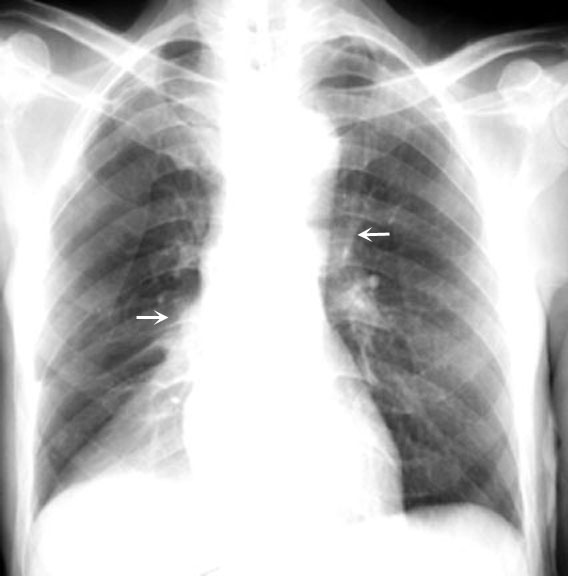

Plate like atelectasis

Plate like atelectasis (sub segmental atelectasis) is an example of focal loss of surfactant.

Note the bilateral basal plate like atelectasis.

This is an example of plate like atelectasis (yellow arrows) in a patient with pulmonary embolism.

You can also encounter plate like atelectasis whenever there is basal hypo ventilation.

• Post-op

• Obesity